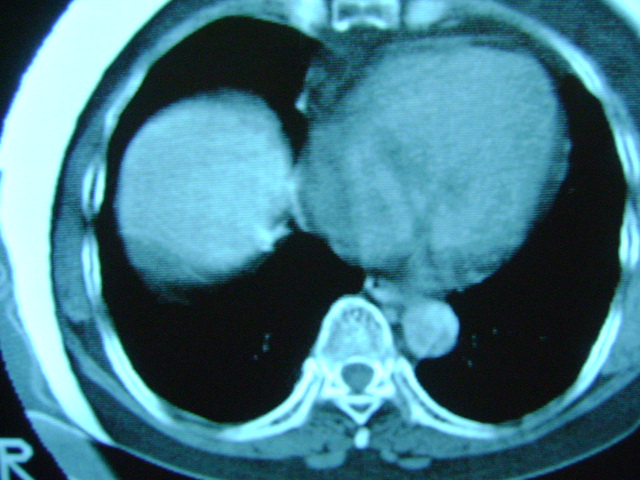

朋友的母亲,56y,咳嗽三个月,感觉左肺门不对,请大家给点意见

不放心可追踪复查。

扫描所示未见明显异常!建议结合临床

扫描所示未见明显异常